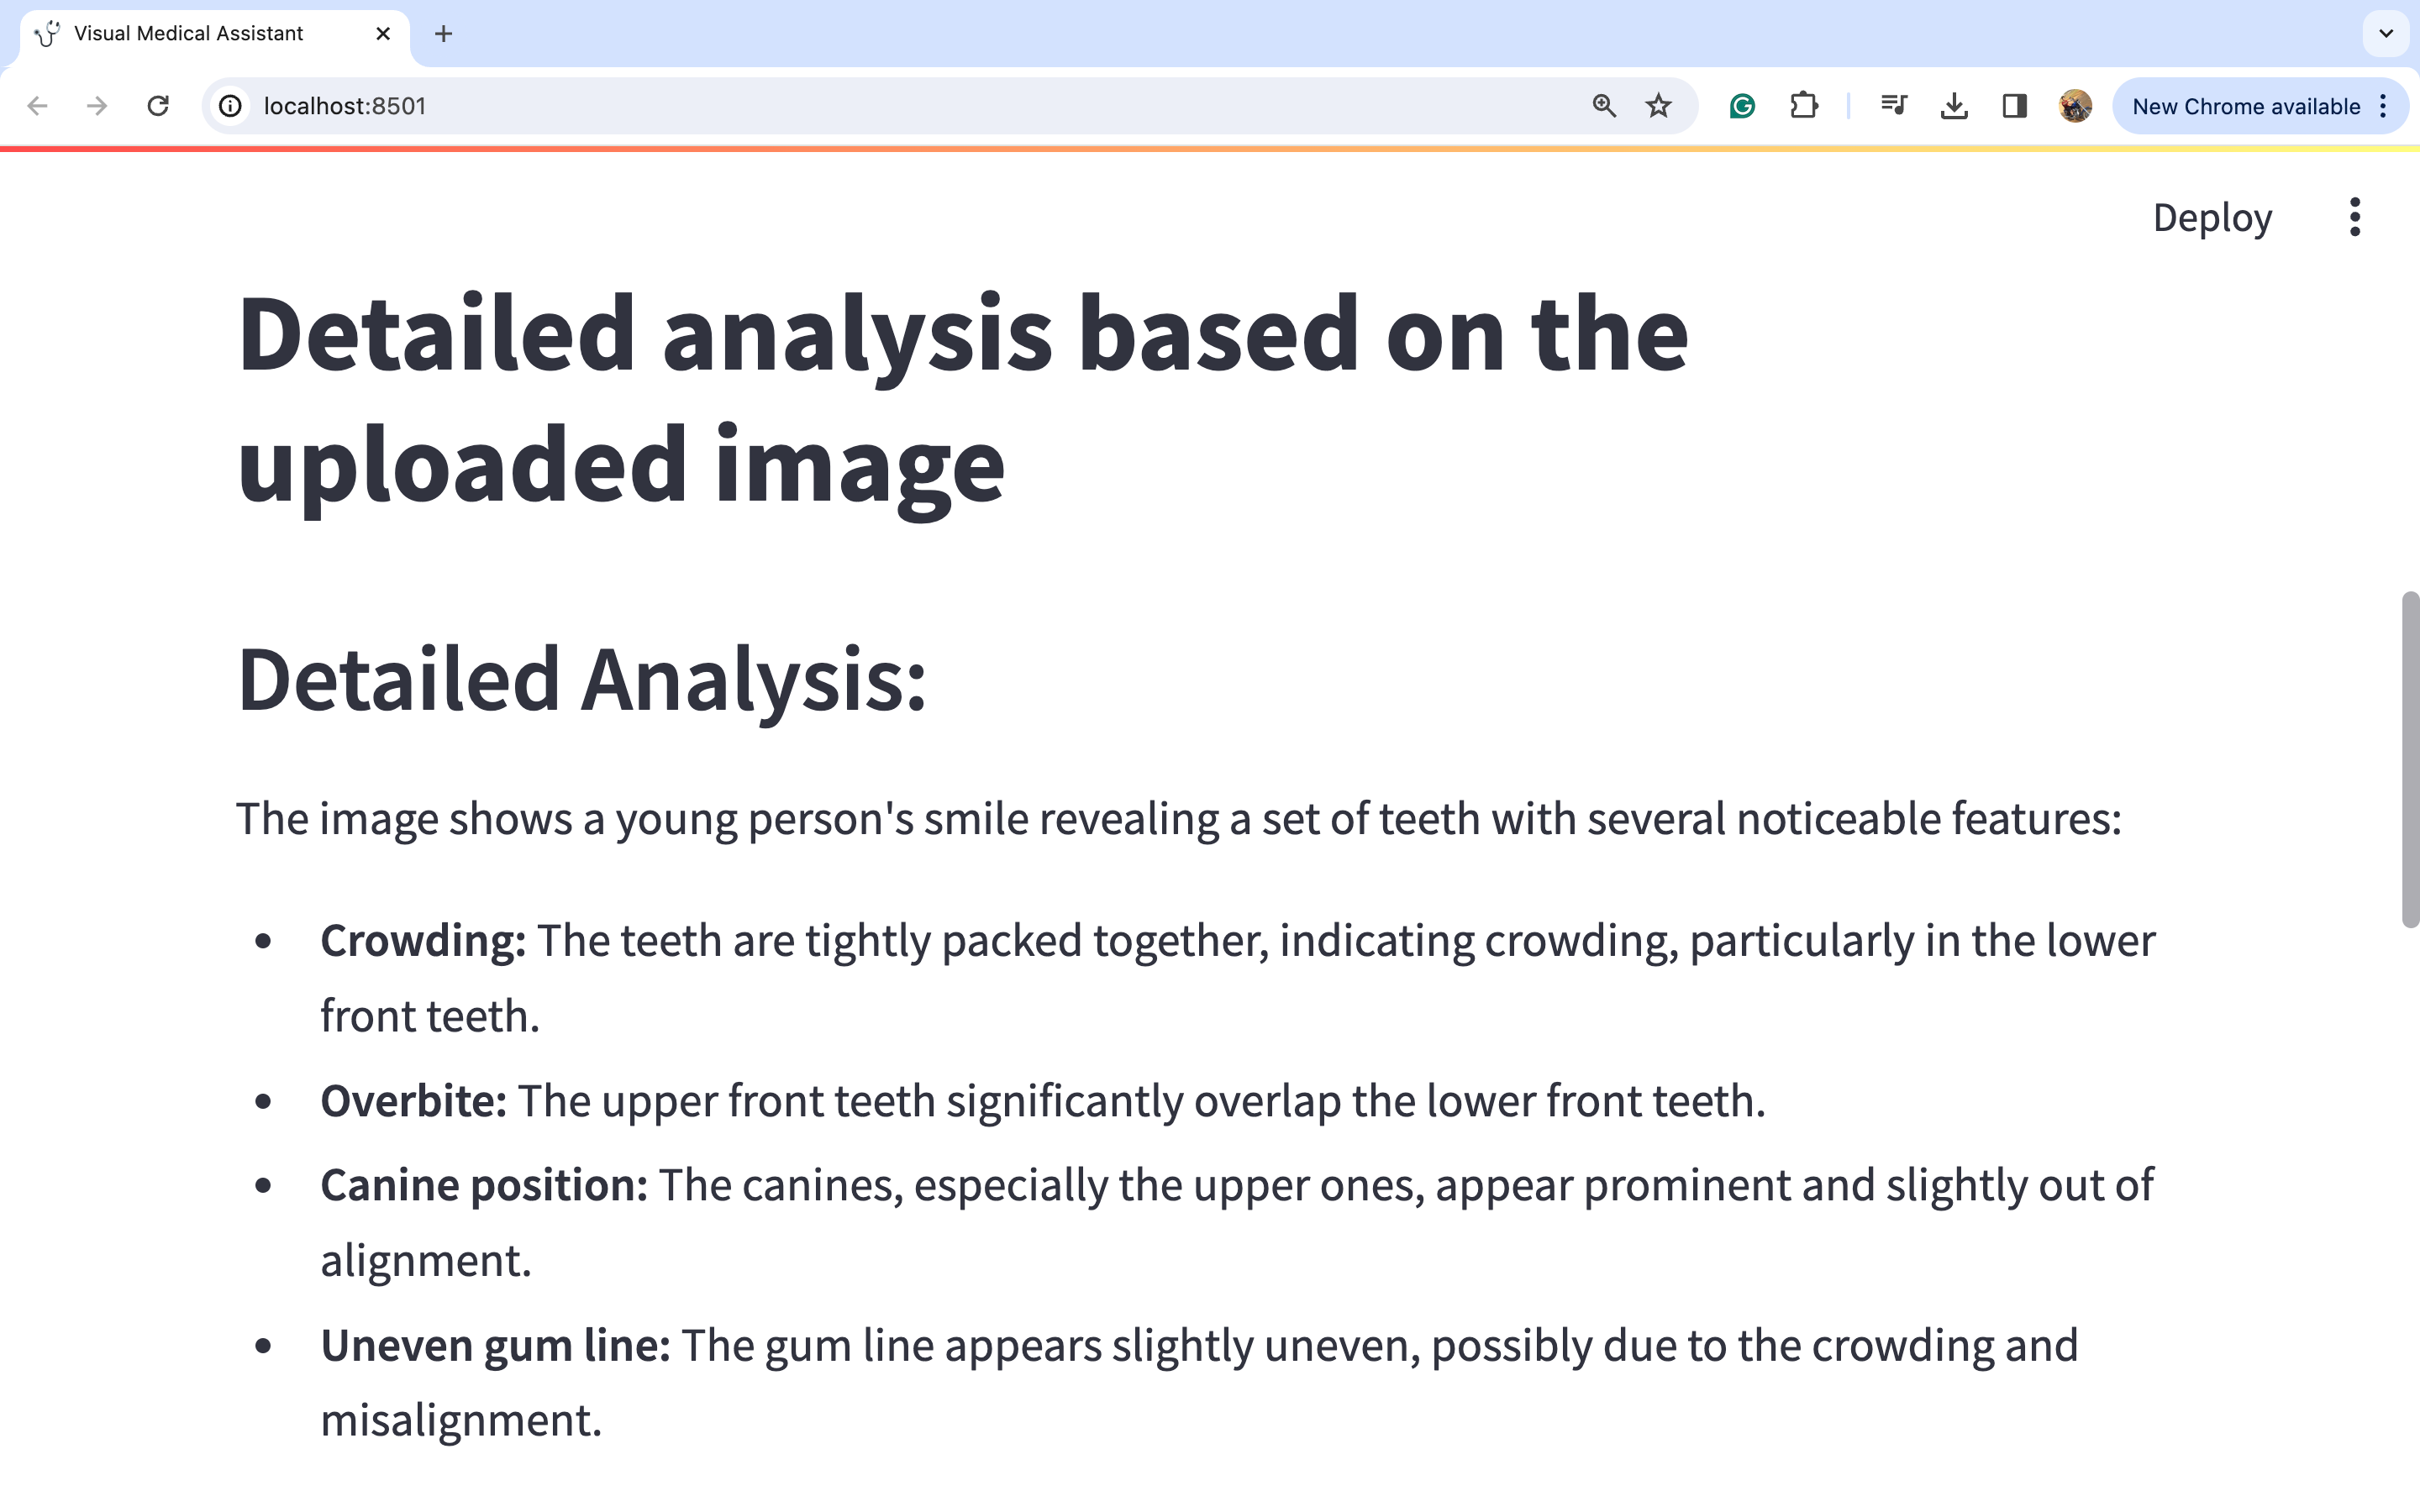

图片1:

通过仔细观察图片,我们可以对潜在的医疗诊断进行深入分析。此外,考虑到这与牙齿问题有关,建议的行动方案是咨询正畸医生并进行一些牙齿X光检查。此外,在这种情况下,佩戴牙套和保持器等多种治疗选择似乎是明智的选择。